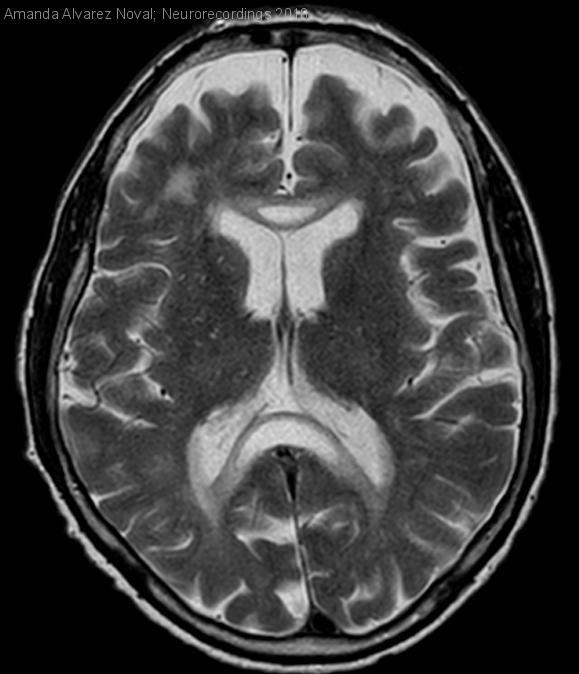

Enfermedad de Marchiafava-Bignami

Hombre | 60 años

Diagnóstico final: Enfermedad de Marchiafava-Bignami

Varón de 60 años que presenta al despertar pérdida de fuerza y sensibilidad en extremidad superior izquierda. Entre sus antecedentes destacan enolismo crónico, tabaquismo, hipertensión arterial, polineuropatía sensitiva y atrofia cerebelosa con ataxia de la...